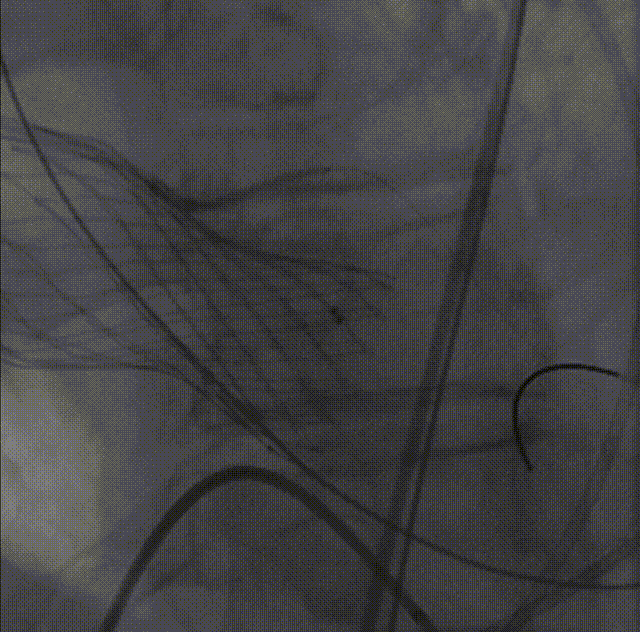

26VenusAplus+snare

瓣膜内22mm球囊后扩张,左冠无显影

LM烟囱支架植入4.0*30mm